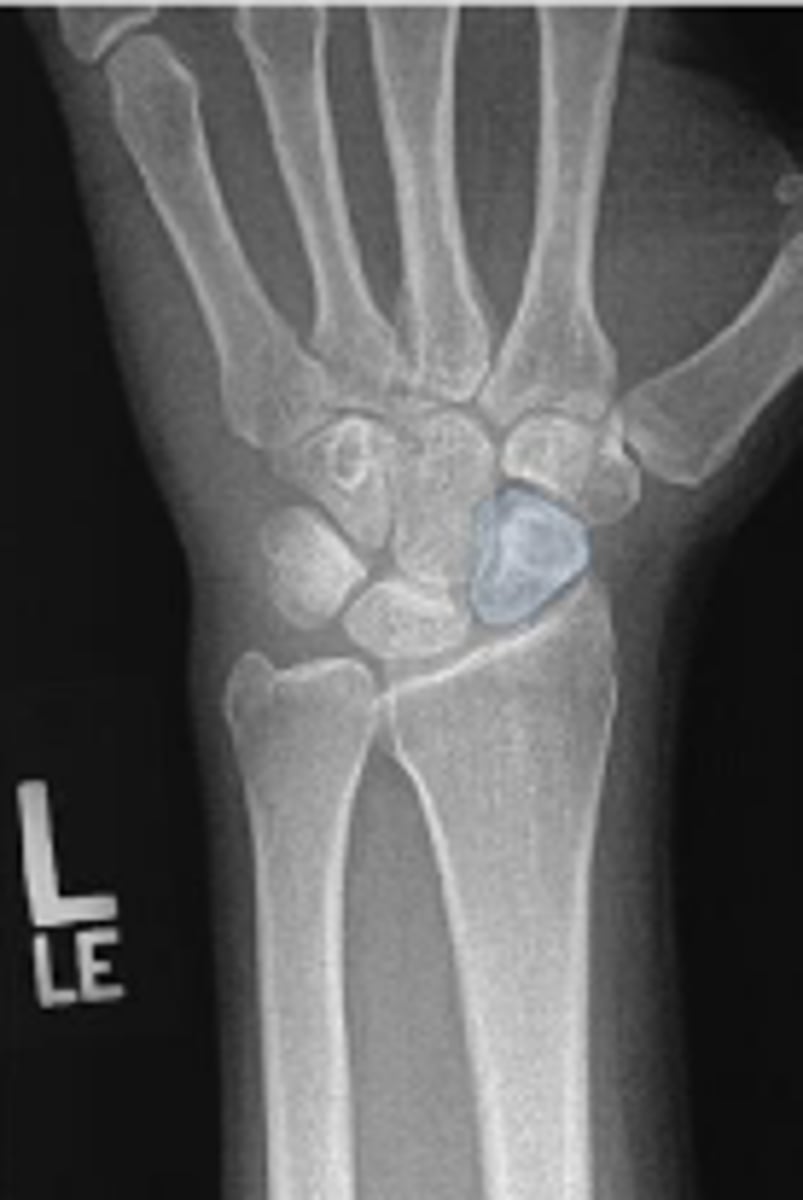

Medial oblique of the left wrist

What is the name of the radiographic view?

Left lunate

What is outlined?